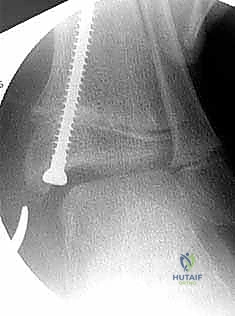

A contraindication for cheilectomy with microfracture is the stiff joint of types 3 and 4 osteoarthritis. In this case, in patients with a low activity level who want good ROM, a resurfacingtype prosthesis (not a “head resection” type) is a good alternative and is being used with increasing frequency (FIG 2A).

Patients with isolated, painful osteochondral lesions without degenerative joint disease may be considered in rare cases for microfracture alone (for a small, contained lesion) or for an osteochondral transplantation from the plantar medial talus (FIG 2B,C).

FIG 2 • A. Postoperative radiograph of first MTP joint prosthesis. B,C. Osteochondral autograft transplantation from the plantar medial talus.*